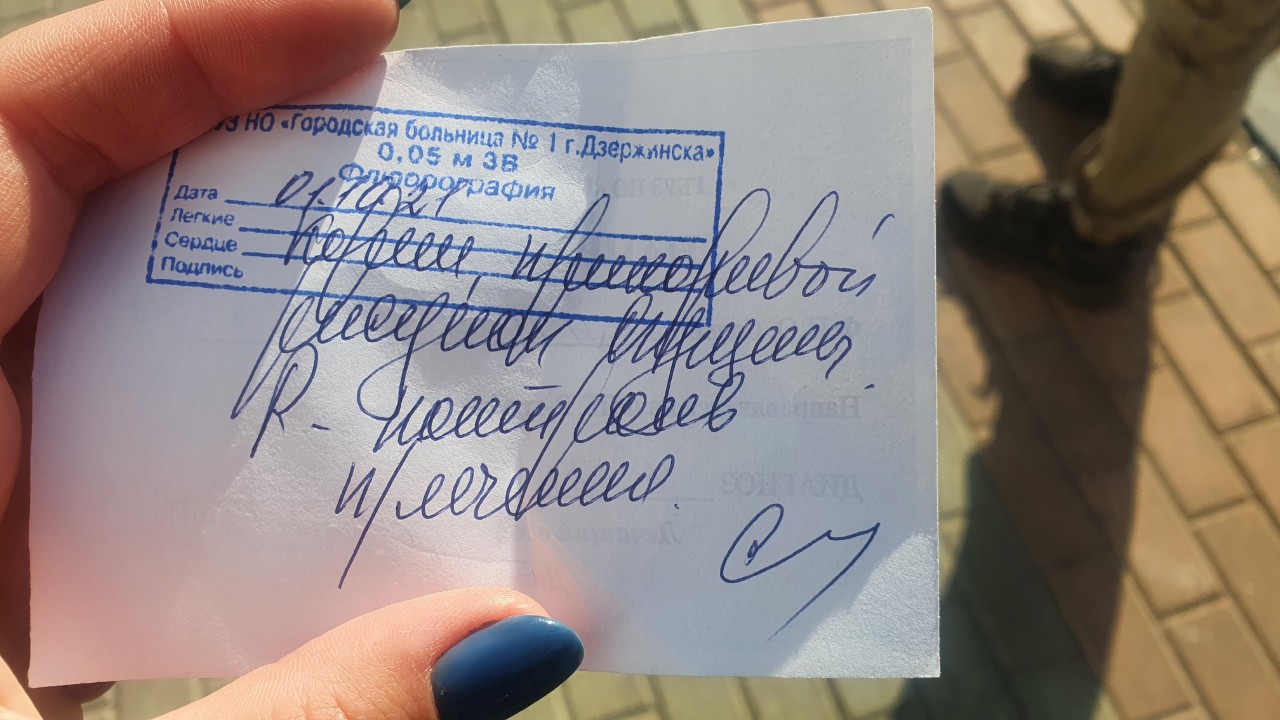

Фотографии рентгеновских снимков без необходимости направления от врача